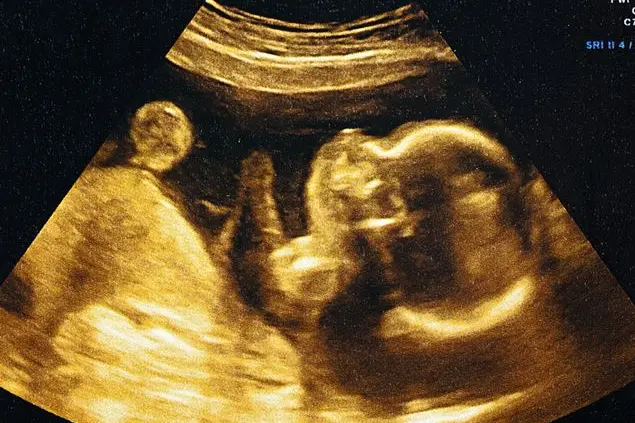

«La protezione dei bambini costituisce, giustamente, lo scopo costitutivo di molte istituzioni pubbliche e private, nazionali ed internazionali. Nell’anniversario della Convenzione internazionale sui diritti dell’infanzia (Onu 20 novembre 1989) il Movimento per la Vita Italiano ricorda a tutti che bambini sono anche coloro che viaggiano verso la nascita. La Convenzione getta, infatti, uno sguardo anche all’infanzia che precede la nascita: "il fanciullo, a causa della sua immaturità fisica e intellettuale, ha bisogno di una particolare protezione e di cure speciali compresa un’adeguata protezione giuridica, sia prima che dopo la nascita". Dunque, il bambino è bambino anche nella fase prenatale».

E ancora: «Le testimonianze di scienziati, giuristi, filosofi e bioeticisti a favore della tesi che i concepiti non ancora nati possono essere chiamati e sono “bambini” sono autorevoli. Ma ci sono le testimonianze ancora più autorevoli delle donne e delle mamme. Allora, nel giorno in cui si celebra la giornata mondiale dell’infanzia, non dimentichiamo i più bambini dei bambini!».